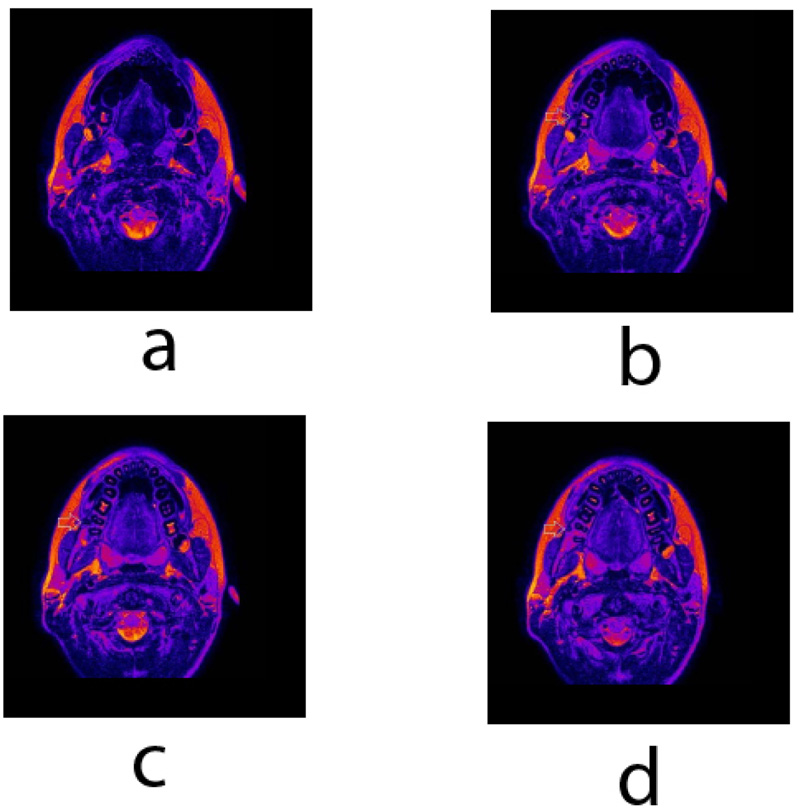

Besides the conventional diagnostic tools, teeth and jaws were scanned using clinical 3T whole-body Magnetic resonance imaging (MRI) system (TX Achieva, Philips, Netherlands) with a maximal gradient strength of 80 mT/m and the use of an S Flex coil. A T2 weighted turbo spin-echo (TSE) imaging in the transversal plane was performed with the following parameters: TR/TE 3000/100 ms, TSE factor 15, matrix 315 x 180, NSA 1, voxel 0.57 x 0.72, and FOV 181 x 144 mm. MRI slice thickness was set at 2.0 mm. MRI scans revealed a unilateral supernumerary root with an independent pulpal canal on the second permanent mandibular molar on the right side. The root is fully separated and is located buccally (Fig. 9). MRI T2 weighted TSE image in the transversal plane shows right second PMM (Fig. 9), its dental pulp extends buccally from the pulpal chamber into a round root – radixparamolaris.

RP was diagnosed using an MRI system. MRI is a sensitive imaging method, which has been previously used for imaging and investigation of dental and periodontal tissues [17, 20, 28, 29]. Two-dimensional radiographic methods such as periapical or panoramic x-rays are (because of possible overlapping of anatomical structures) considered limited tools and less ideal for detecting supernumerary PMM roots [15, 30]. Even though the endoral radiographs are not the most sensitive diagnostic test for supernumerary roots, they are still the most commonly used in dental practice. Several techniques of tube disparallelism in a silicone guide have been proposed in order to improve their diagnostic sensitivity [31].

The use of 3D imaging, e.g., micro-CT or CBCT, enables a more accurate determination of morphological variations such as supernumerary roots [14, 32]. The latter mentioned fact is of clinical importance because supernumerary PMM roots tend to be smaller, curved, and with a higher degree of morphological irregularity [3, 9, 13]. Our case demonstrated MRI to be sensitive and accurate enough to detect morphological variations such as supernumerary roots and can be used to determine the presence and state of the dental pulp in the root canal, as opposed to CT techniques it does not emit ionizing radiation. Therefore MRI may also be used in children during growth and development [33, 34]. A possible limitation of MRI imaging is a longer scan time, besides the higher cost, which might lead to increased patient anxiety or claustrophobia [35, 36].